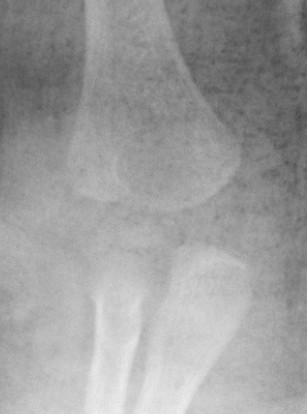

Xray

Distal physis not ossified < 1 year

- radius and ulna lose normal association with distal humerus

- posteromedial displacement of the ulnohumeral joint

- appears like an elbow dislocation

- disruption of radio-capitellar line